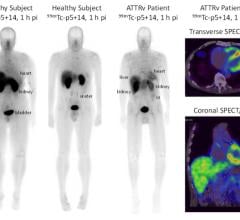

The campus will house large-scale facilities to produce positron emission tomography (PET) imaging agents. When injected into the body, these specialized radiopharmaceuticals, called biomarkers, detect and trace abnormal cellular functions that are associated with a variety of diseases. Visible using sophisticated imaging scanners, these biomarkers make it easier for physicians to non-invasively diagnose critical, life-threatening diseases in their earliest stages. They can also improve physicians’ ability to track the effectiveness of patient treatment plans.

State-of-the-art PET manufacturing facility: The center will house the latest technology in PET manufacturing, including dual cyclotrons, which can be used to produce large quantities of radioisotopes. It will also contain production facilities that allow for the simultaneous radiosynthesis of multiple imaging agents, for both commercial and research purposes.